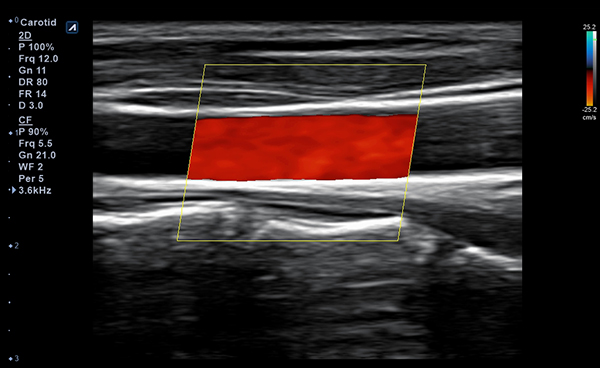

Alpinion Medical Systems, la empresa de sistemas de ultrasonido, ha combinado tecnologías

de procesamiento de imágenes y transductores para garantizar que minisono proporcione

imágenes 2D de alta definición e información de Doppler más claras y nítidas.

minisono ofrece funciones esenciales con el nivel de rendimiento necesario

para garantizar que los exámenes y diagnósticos sean precisos.

- Frequency3-12 MHz

- Dimension (height/width/depth)25.2 / 62.5/ 150mm

- Weight 175g

- Field of view 38.4mm

- Max depth10 cm

- Imaging modesB-mode, CF, M, PW, PD